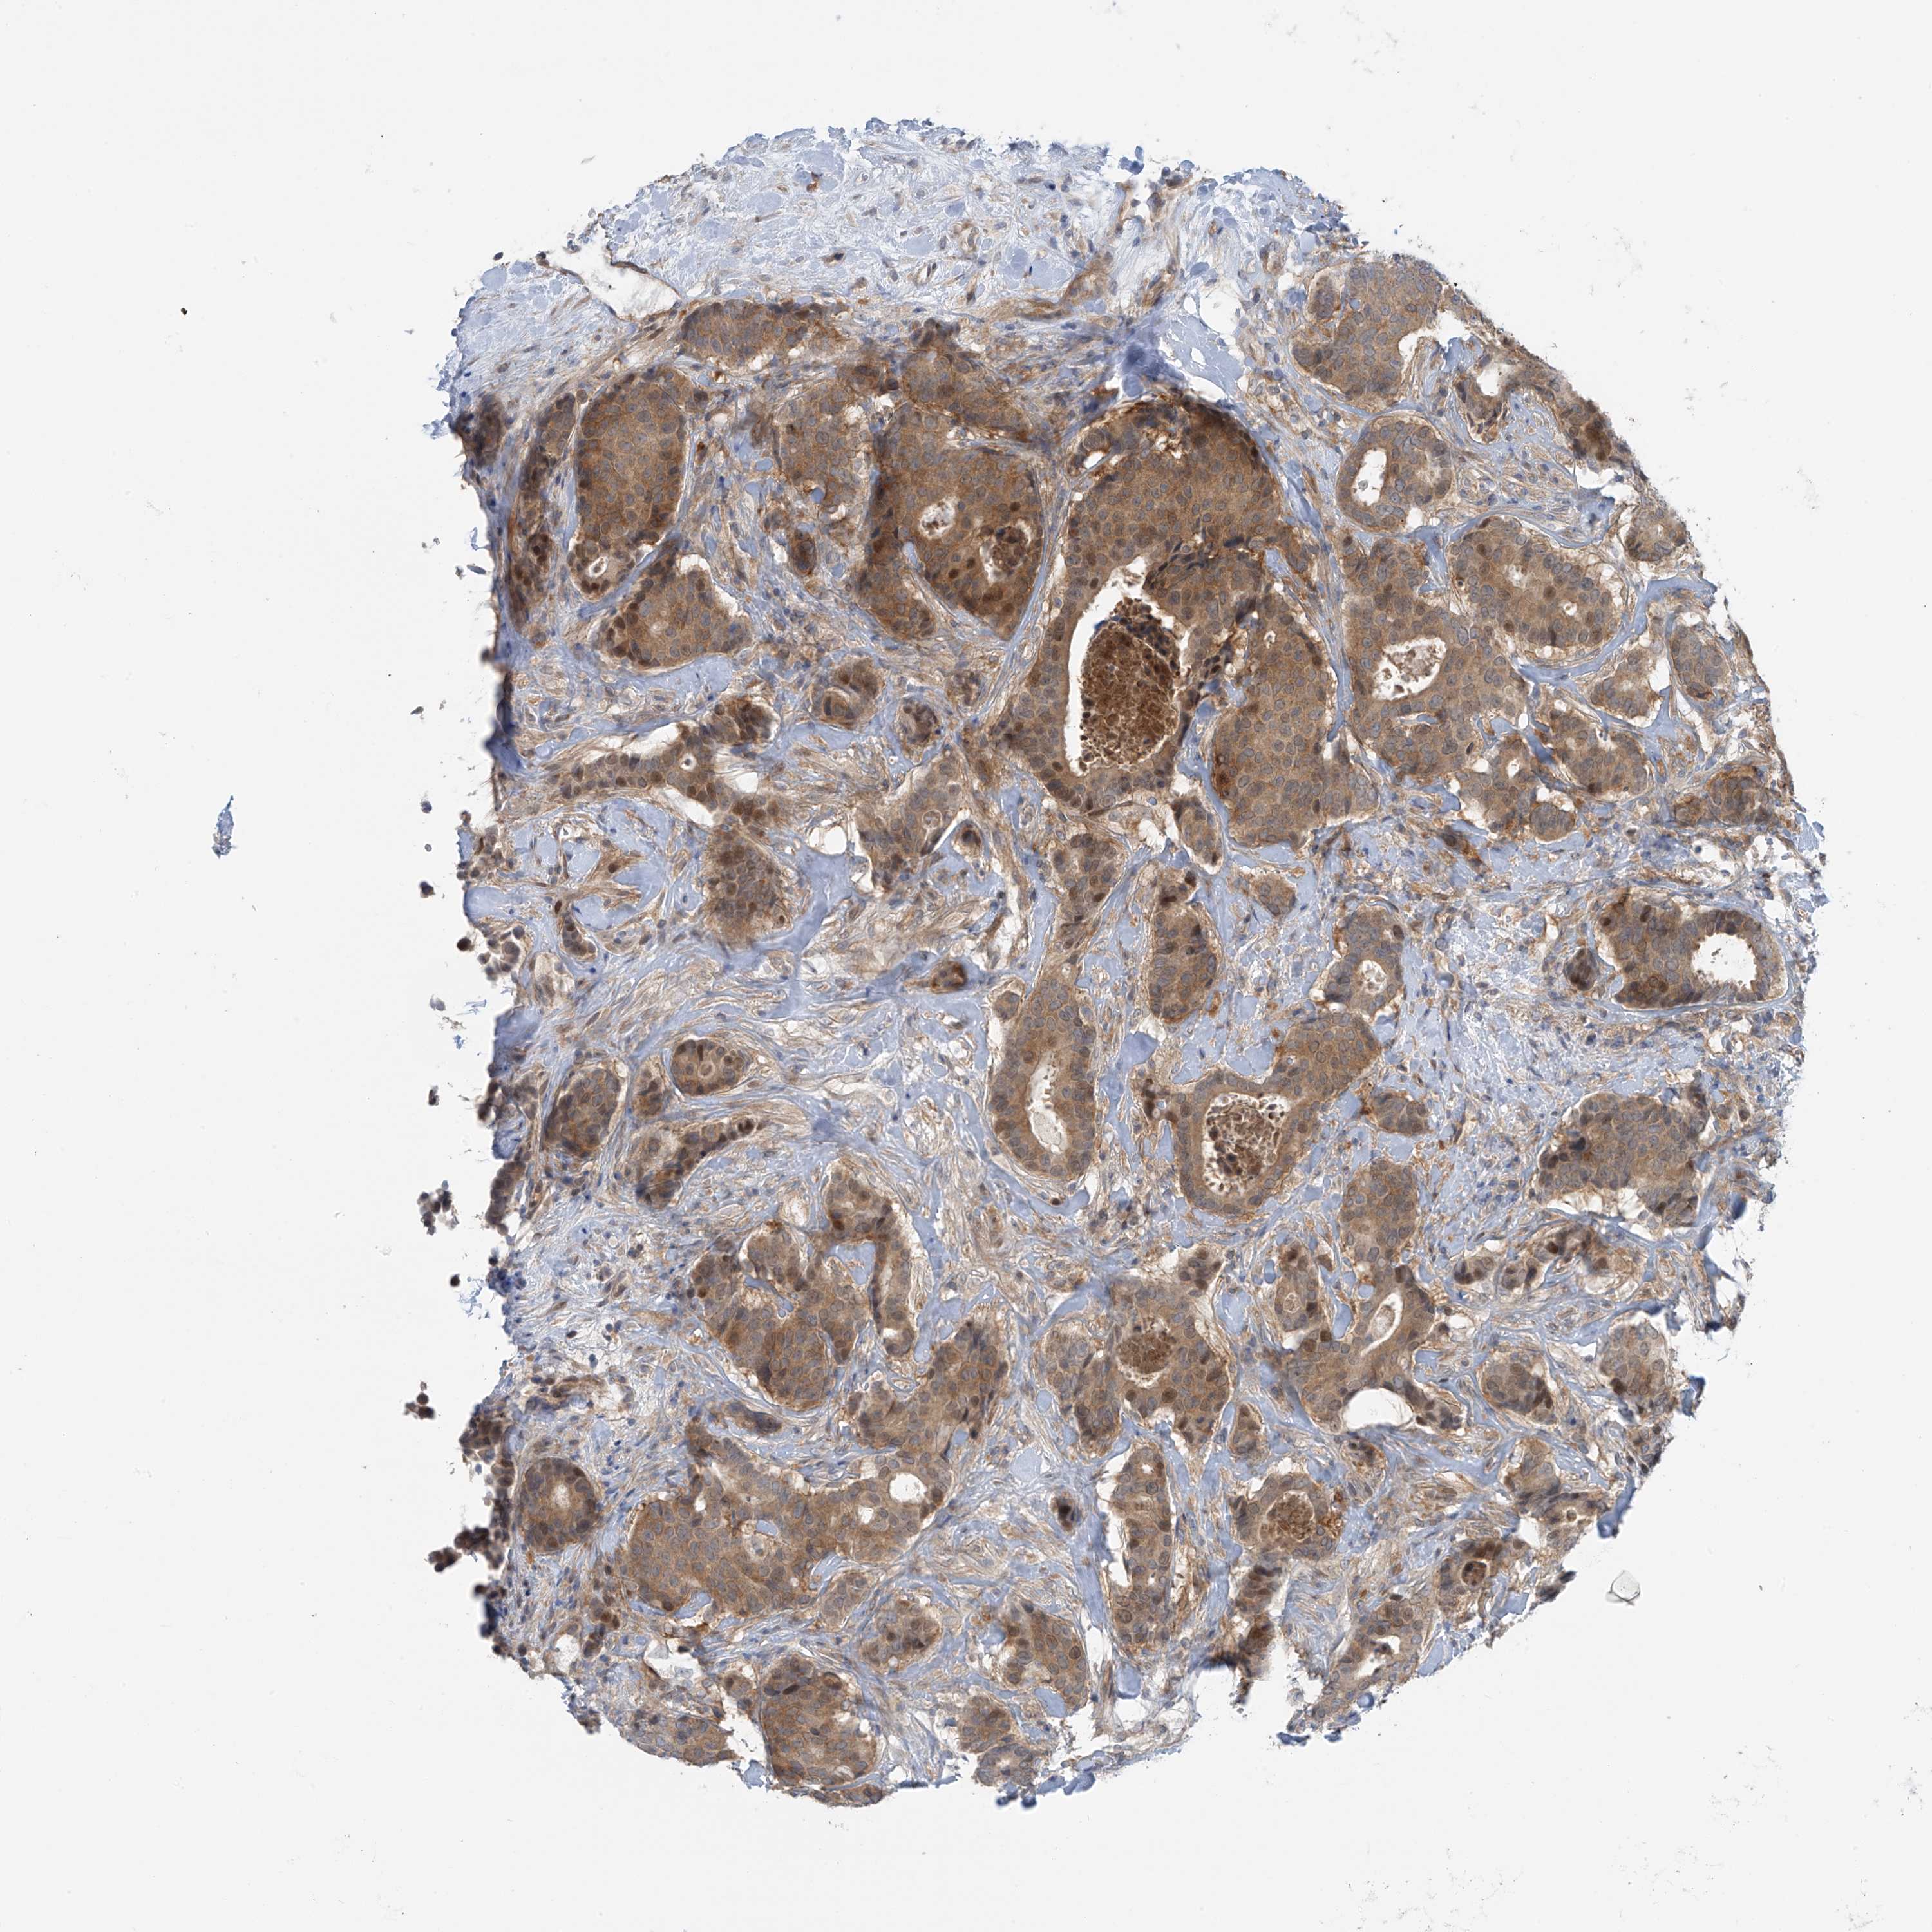

BRCA TCGA BRCA VALIDATION PROTEIN EXPRESSION

Breast cancer

Human cancer